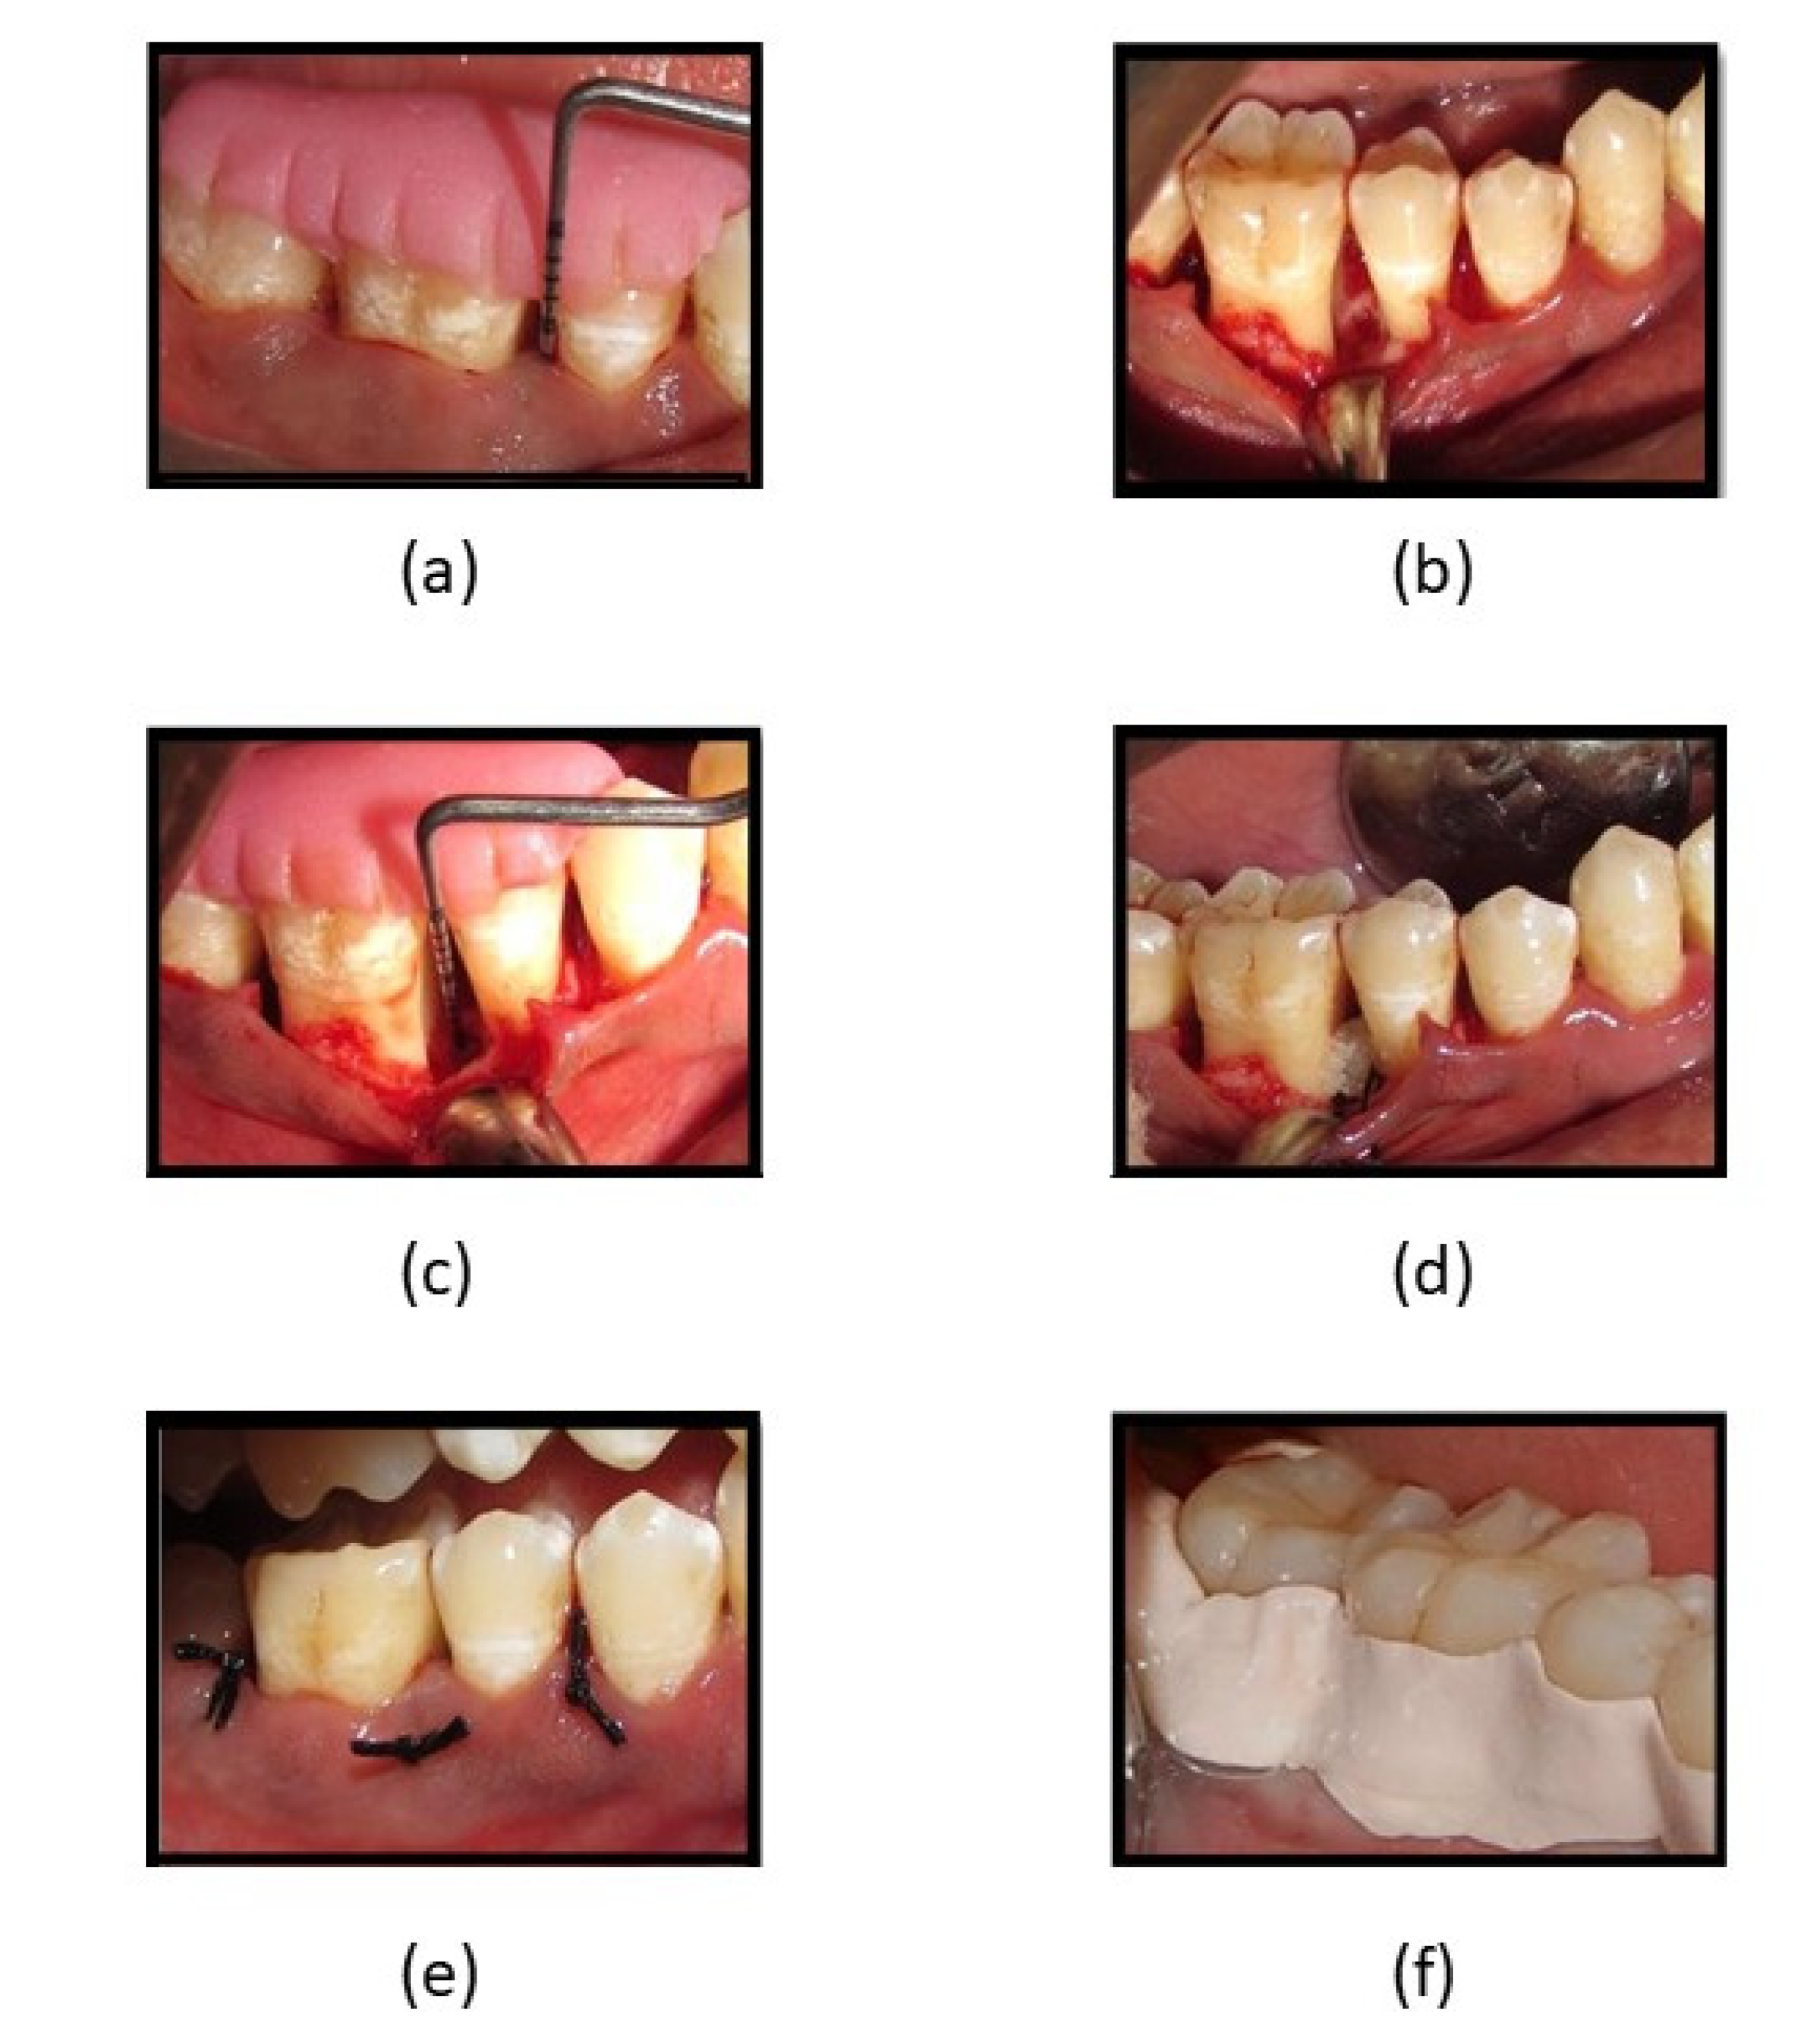

Clinically, in its osteogenic effectiveness in periodontal intra-bony defects management, the mean age of the participants recruited was 43.75 (5.638) years, with a higher percentage of females (60%, n = 24) (Table 3). Statistically significantly lower plaque index scores were observed in both groups at 6 and 9 months as compared to baseline (p < 0.05), while significantly lower scores in all other clinical parameters were observed at all three-time intervals when compared to baseline in both groups. Intergroup analyses showed significantly lower scores were observed in the GCF group at 3 and 6 months, while both groups were comparable at 9 months (Table 4). A statistically significant reduction was observed in radiographic parameters at 9 months in both groups (p < 0.05). A higher defect fill was seen in the fucoidan-chitosan group at 9 months, with lower CEJ-base measurement (Table 5). The clinical and radiographic improvement is shown in Figure 5.

Figure 5. (a) Reduction in PPD at 3 months in fucoidan-chitosan group; (b) reduction in PPD at 6 months in fucoidan-chitosan group; (c) RVG image of intra-bony defect at baseline in fucoidan-chitosan group; (d) RVG image of improvement in intra-bony defect at 9 months in fucoidan-chitosan group; (e) RVG image of intra-bony defect at baseline in CGF group; (f) RVG image of intra-bony defect at 9 months in CGF group.